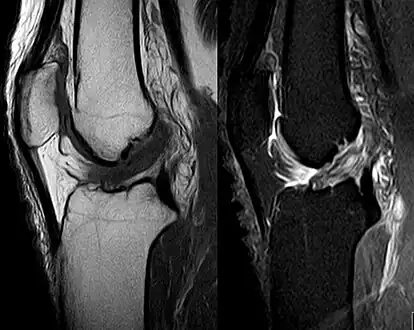

ACL tear

Medical imaging

Though clinical examination in experienced hands can be accurate, the diagnosis is usually confirmed by magnetic resonance imaging, which provides images of the soft tissues like ligaments and cartilage around the knee.[1] It may also permit visualization of other structures which may have been coincidentally involved, such as the menisci or collateral ligaments.[29] An x-ray may be performed in addition to evaluate whether one of the bones in the knee joint was broken during the injury.[9]

MRI is perhaps the most used technique for diagnosing the state of the ACL, but it is not always the most reliable technique as the ACL can be obscured by blood that fills the joint after an injury.[30]